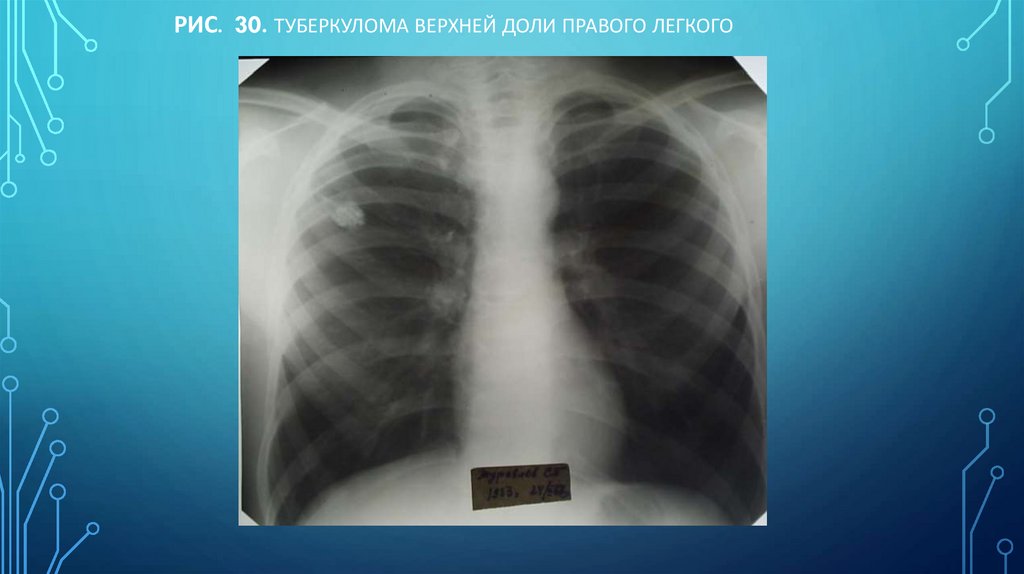

Рис. 30. Туберкулома верхней доли правого легкого